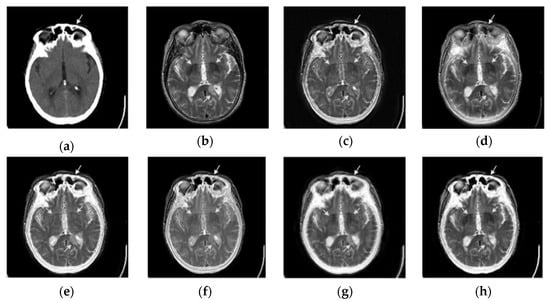

2.2. Proposed Fusion Strategy

2.2.1. Robust Edge Analysis

2.2.2. DLCNN-based Fusion Network